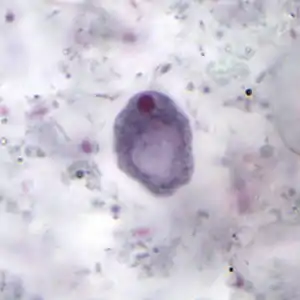

Cyst

The cysts are 8–10 micrometres in diameter, with a thick wall and a large glycogen vacuole that stains darkly with iodine. Usually harmless, it may cause amebiasis in immunologically compromised individuals.

[5][6] As the second form of I. butschlii, cysts have an oval shaped- single nucleus with a prominent nuclear endosome. This form is also large, single, glycogen-filled vacuole called iodinophilous vacuole (glycogen stains with iodine). Cysts are the infective stage of I. buetschlii. Unlike trophozoites, cysts are often found in formed stools.[4]